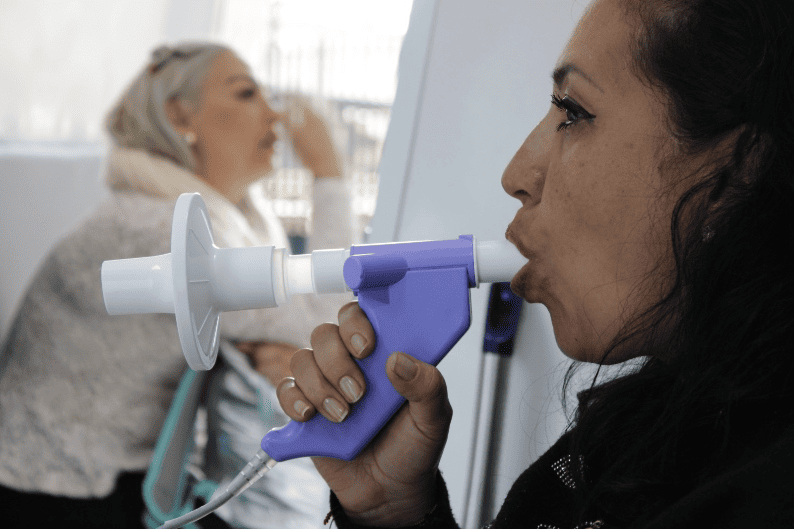

La espirometría es una prueba sencilla y no invasiva que mide la capacidad y el flujo de aire en los pulmones, ayudando a diagnosticar y monitorear enfermedades respiratorias como asma, EPOC y fibrosis pulmonar. Sus beneficios incluyen la detección temprana de afecciones pulmonares, la evaluación de la respuesta al tratamiento y el control preciso de la función respiratoria, mejorando la calidad de vida del paciente.